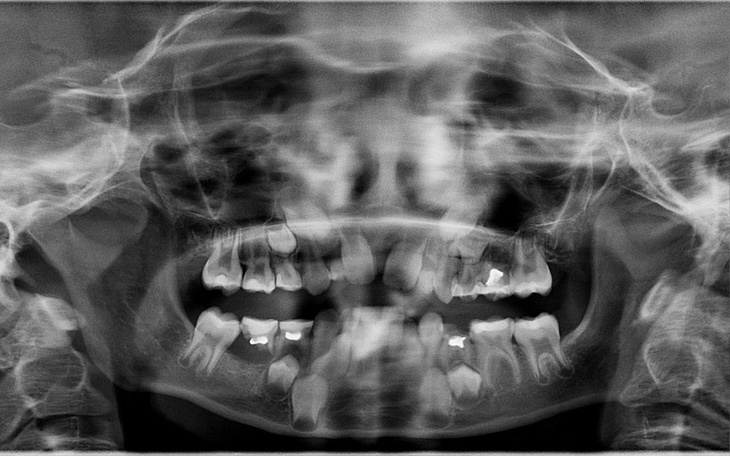

Na zdjęciu są mleczaki i jak ktoś sie zna tylko kilka zębów stałych. Oligodoncja choroba ta jest wrodzonym brakiem zębów występuje u 0,01 do 0,03 procent populacji no niestety przytrafiło się to mojej córce. Istnieje zagrożenie że inne organy mogą nie funkcjonować gdyż przeważnie jest to jakoś powiązane. Na szczęście nic na razie nie wykryto. Brakuje jej 14 zębów stałych tak 14. Nie chce dodać zdjęcia żeby koleżanki się z niej nie naśmiewały gdyż dzieci bywają okrutne względem siebie. Na razie tego nie widać wiadomo mleczaki wypadają. Oczywiście w okolicy nie ma nikogo kto by się znał na takim przypadku- dentyści fajnie są mili, oznajmili że jedynie czytali z książek o takim przypadku osobiście żadnego nie widzieli aż do momenty gdy zobaczyli moją córkę. Muszę dojeżdżać z nią jakieś 250 km na leczenie do Pani Doktor i to standardowo w naszym Państwie prywatnie. Na razie leczenie będzie polegało na rozszerzaniu położenia zębów jakiś aparat a potem na wstawieniu implantów. Aparat dojazdy jakoś udźwignę z wypłaty ale implanty.... Sam implant - to jakieś 2400-3000 plus "ząb-korona" jakieś 1000-1300 zł. Wiem że dużo ludzi ma pewnie cięższą sytuację ode mnie ale jak ktoś może to niech podzieli się czym może Mam nadzieje że do jej 18 dozbieram potrzebne pieniądze.